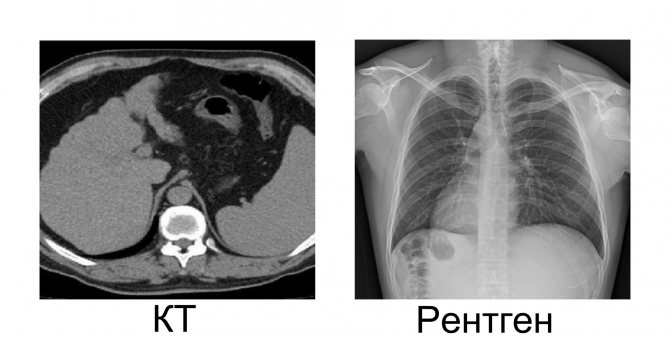

Основное различие между рентгеном и томографией — это путь рентгеновского излучения через исследуемый объект и способ получения изображения.

Рентгеновские лучи проходят через биологический объект только один раз, поэтому получается плоское однослойное изображение. Тени от органов могут накладываться друг на друга, что мешает диагностике.

КТ-сканер делает несколько снимков под разными углами на разных уровнях. Серия изображений, обработанных компьютерной программой, преобразуется в трехмерное изображение, которое отображается на мониторе. Органы не перекрываются, хорошо видны мягкие ткани и их структура.

Однако это однослойное плоское изображение. Диагностические проблемы возникают, когда тени крупных органов перекрывают исследуемую область.

Благодаря томографии получается больший объем достоверной и значимой информации для диагностики. Трехмерное изображение может учитывать расположение поражения, его характер и взаимосвязь между поражением и окружающими тканями. Высокая точность метода позволяет обнаруживать патологию на самых ранних стадиях.